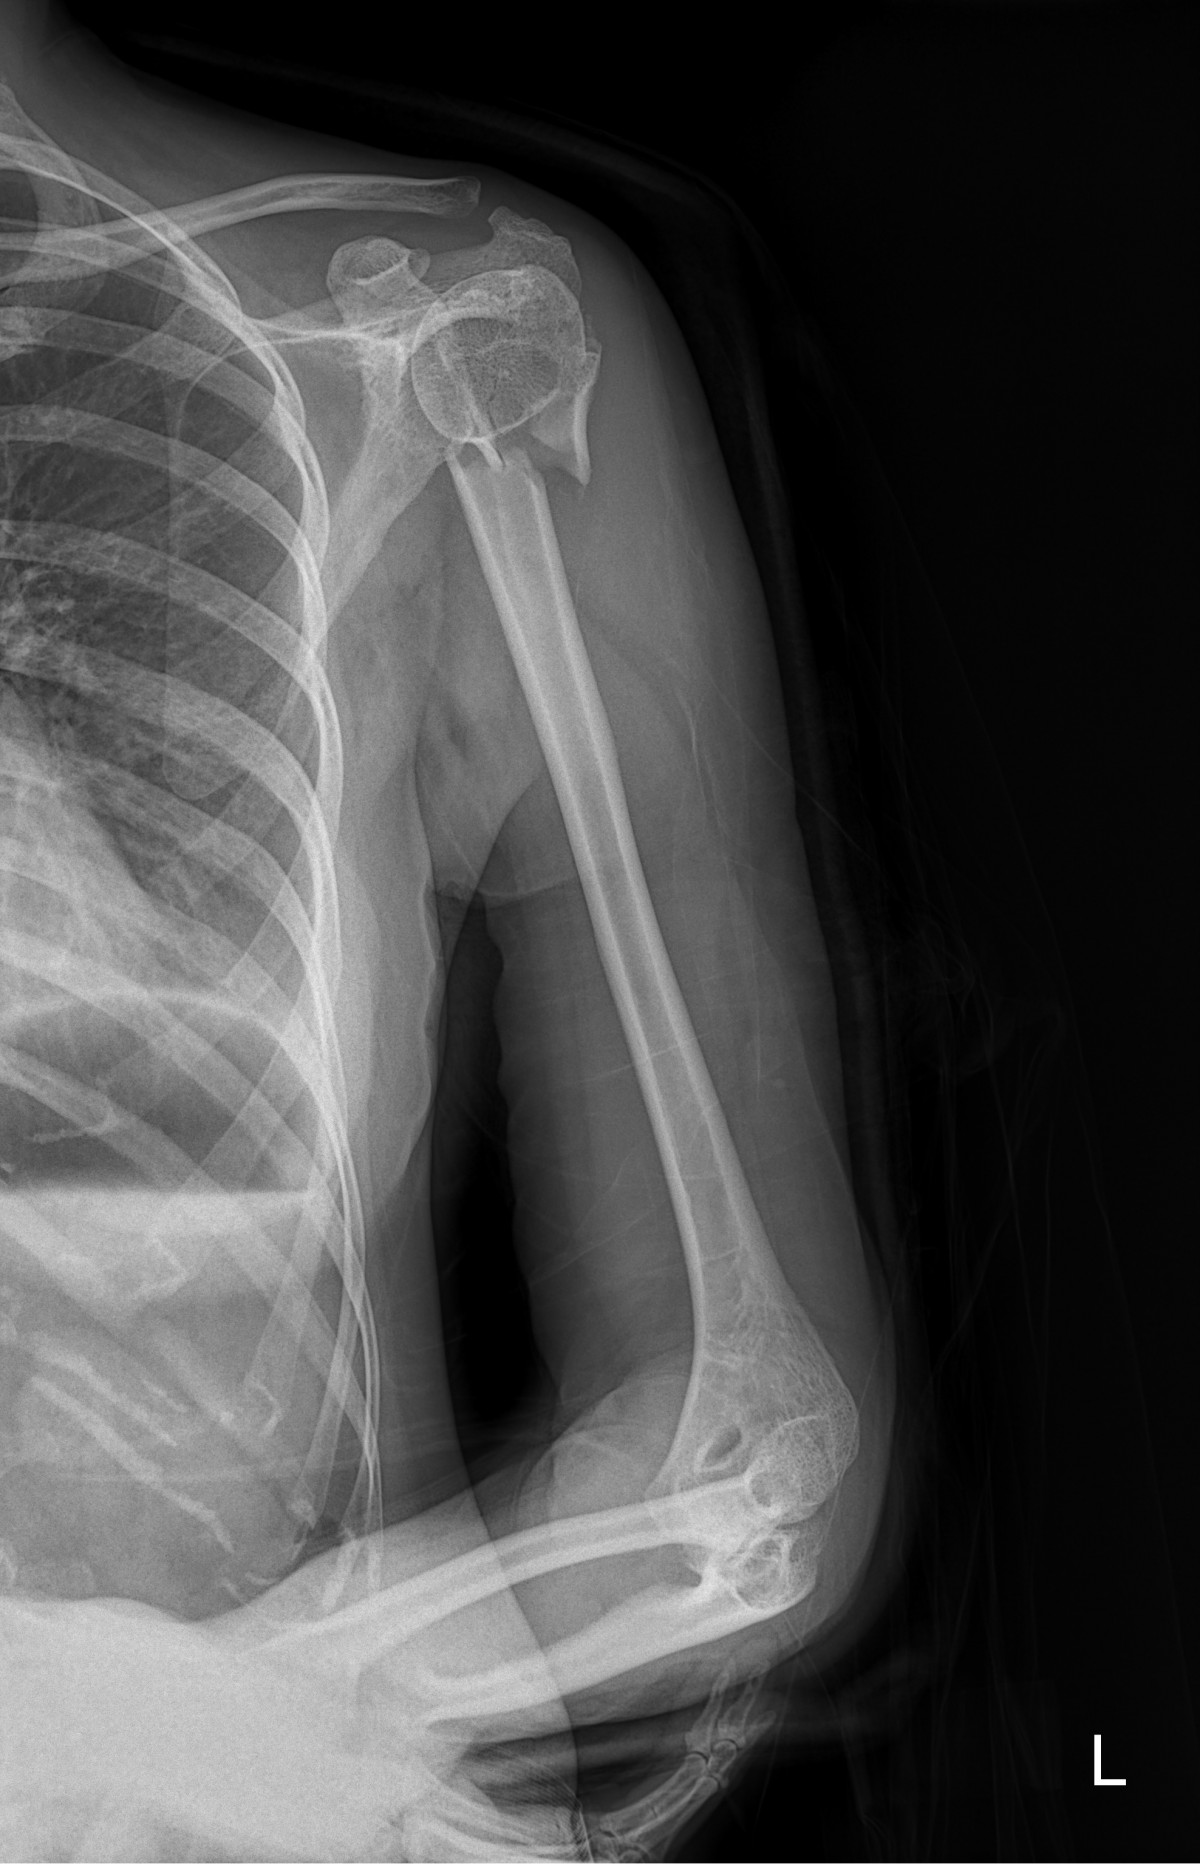

이재상원장님 어깨 골절 수술 구미O 환자

dae765e4d9ac96aee867c9d6292d8784_1758002752_9148.jpg